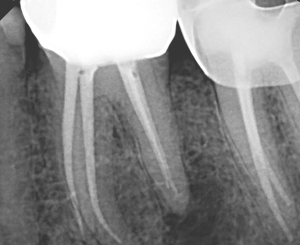

When I see a lateral radiolucency on the furcation side of a mesial root of #19 or #30 (Fig 1: around the junction of the middle and apical 1/3), I highly suspect a middle mesial (MM) canal that exits laterally.

Re-treatment was performed, and the MM canal was identified, instrumented and obturated. The final radiographs show that the lateral lesion corresponds with the MM canal and its lateral exit point (Fig 3 and 4).